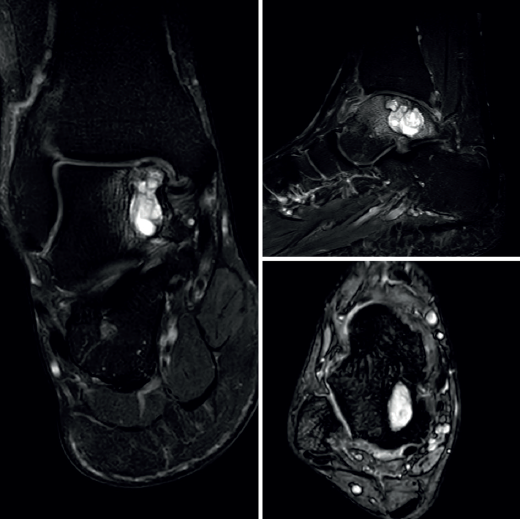

El estudio por resonancia magnética (RM) mostraba un comportamiento de la señal isointenso al líquido en todas las secuencias, con múltiples tabiques que le conferían un aspecto multilobulado (Figura 2).

El complejo del ligamento lateral externo, el ligamento deltoideo y la sindesmosis tibioperonea no presentaba alteraciones.

En las pruebas de imagen, la RM es la que mejor caracteriza estas lesiones. Muestra una señal hiperintensa en T2W, pueden delinearse niveles llenos de líquido y observarse múltiples septaciones internas. Permite valorar su extensión perilesional y el edema circundante. La TAC es útil para determinar la presencia de una fractura patológica.